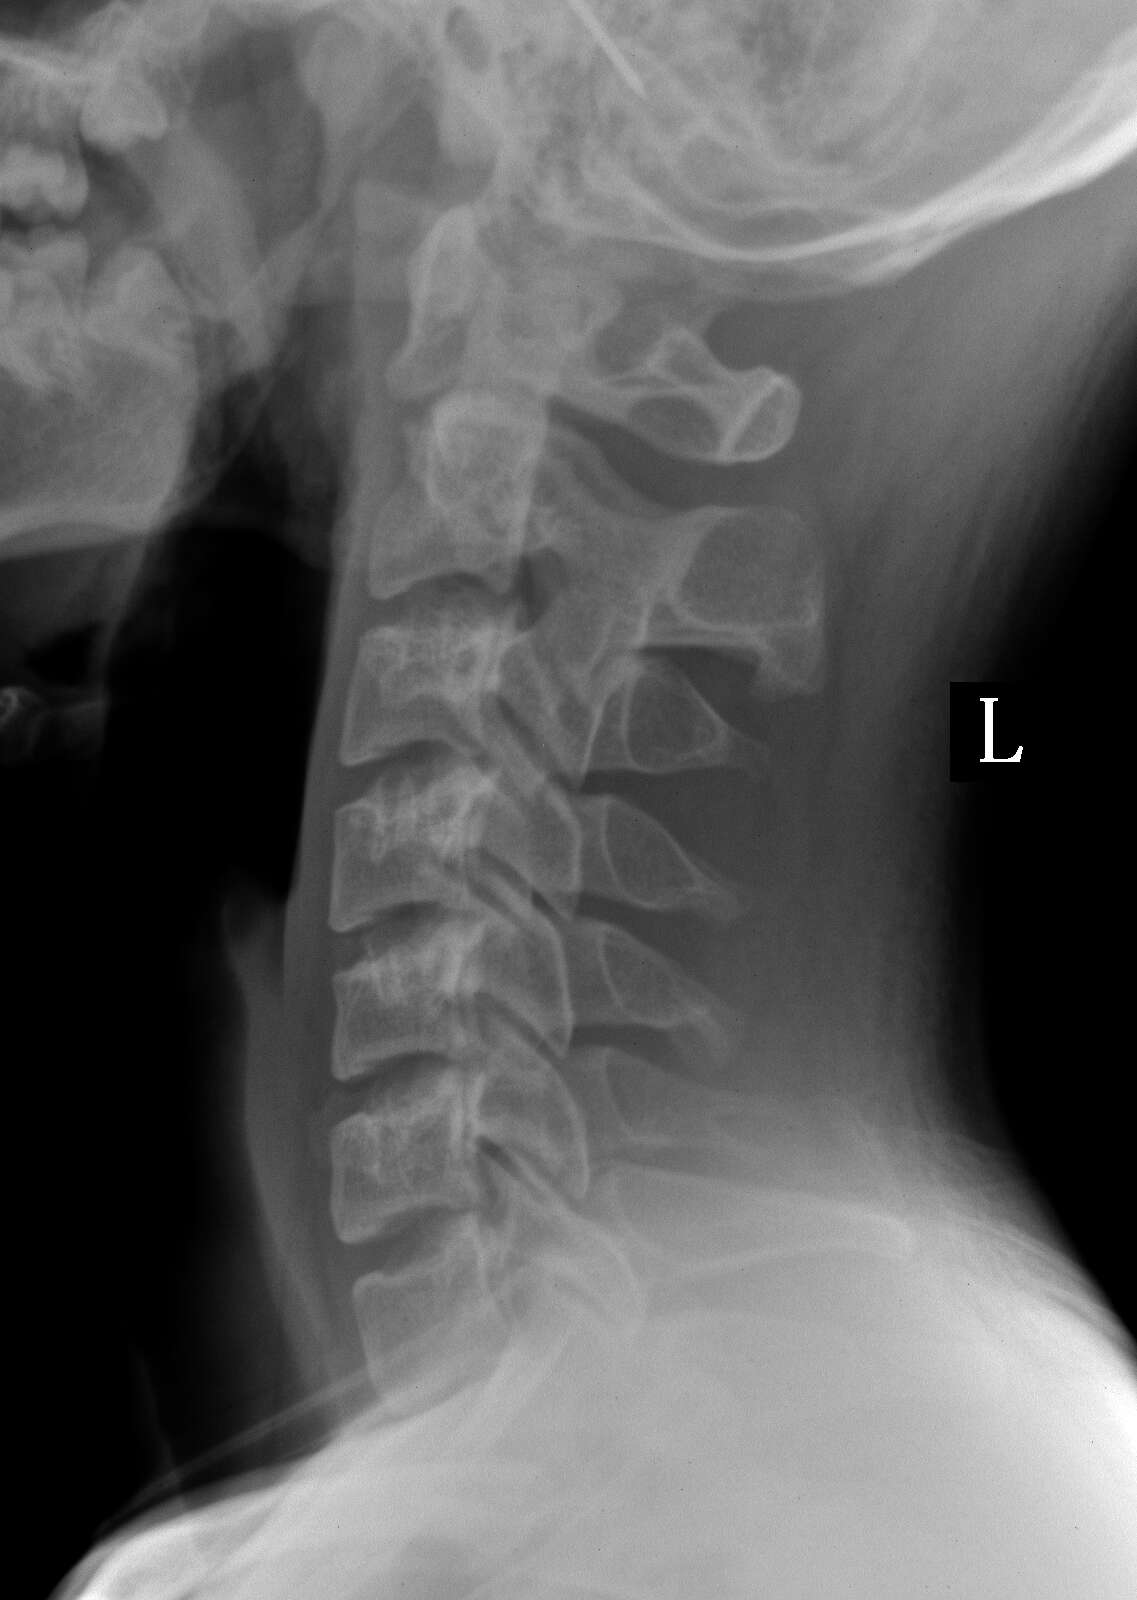

患者,男性,20y,常脖子酸痛来检

画的那四个圆圈里面是否有事,还是拍片时角度问题